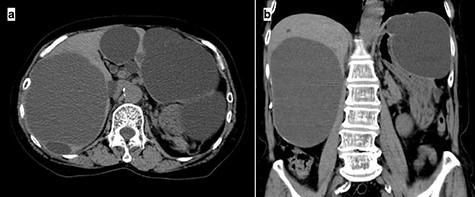

A 74-year-old woman presented with right upper abdominal pain and poor dietary intake. She had no notable medical history or history of abdominal trauma. Abdominal computed tomography (CT) showed multiple liver cysts, with the size of the largest cyst in the right lobe measuring 155 × 113 × 106 mm (Fig. 1a). In addition, a large cyst measuring 135 mm in the left lateral lobe strongly compressed the stomach (Fig. 1b). T1-weighted magnetic resonance imaging revealed different findings in the right and left lobe cysts, and there were no enhanced structures in the liver cysts (Fig. 2). Positron emission tomography-CT did not show increased 18F-fluorodeoxyglucose metabolism in any of the liver cysts (Fig. 3). Moreover, hepatobiliary scintigraphy with CT showed no biliary communication with the liver cysts (Fig. 4). The patient was diagnosed with symptomatic and multiple liver cysts with no biliary communication or malignancy. Therefore, LF was performed.

Preoperative CT imaging demonstrating multiple large liver cysts in the bilateral liver lobe and compression of the stomach due to a large cyst (a: axial section, b: coronal section).